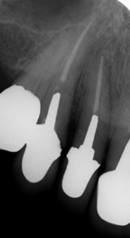

徐々に歯槽骨ももろくなり、歯周病や歯を失うリスクも高まります。

プロテタイトは、骨そのものです。(視覚的にも海綿骨とそっくりです)

骨に良い栄養を取り(骨ケア)、姿勢を正してよく嚙むことことは、下顎骨に刺激が加わり丈夫に(マウスケア)、さらに、